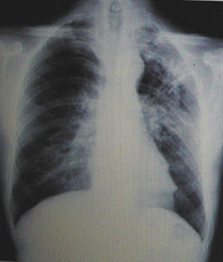

男性,23歲,午后低熱2周。

A.左上肺炎

B.左上支氣管擴(kuò)張

C.左上浸潤型肺結(jié)核

D.正常胸片

『正確答案』C